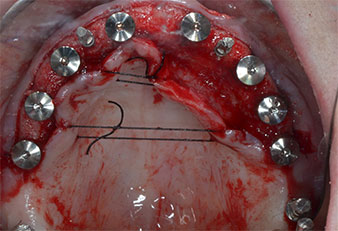

Tre anni dopo era il momento di una protesi dentaria mascellare dello stesso tipo. In base alla pianificazione con CBCT, il rialzo del seno mascellare è stato evitato con l'ausilio di impianti corti e una dima chirurgica è stata utilizzata per trasferire le posizioni pianificate alla cresta alveolare (Figg. 1 e 2).

Posizioni dell'impianto

Fig. 2: dopo l'incisione crestale sulla linea mediana e la preparazione dei lembi mucoperiostei, le posizioni dell'impianto vengono trasferite all'osso.

A causa dell'osso relativamente duro (D2) in quest'area, le sedi dell'impianto di 10 mm nelle posizioni 11 e 21 sono state finalizzate con un trapano rotante da 4 mm di diametro, in combinazione con un contrangolo chirurgico W&H WS-75 L, il motore per impianto W&H Implantmed e il modulo opzionale Osstell ISQ di W&H. Al contrario, a causa dell'osso morbido, le sedi posteriori sono state preparate a un diametro finale di 3 mm utilizzando lo strumento Piezomed I3P. Gli impianti sono stati infine posti per via transgengivale sull'osteointegrato per tre mesi (Figg. 6-10). La protesi dentaria esistente è stata mantenuta su quattro impianti provvisori (Fig. 8).

Impianto a livello tissutale da 10 mm

Fig. 6: un impianto a livello tissutale da 10 mm è posto in posizione 21. L'impianto in posizione 11 e i tre impianti posteriori da 4 mm sono già in posizione.